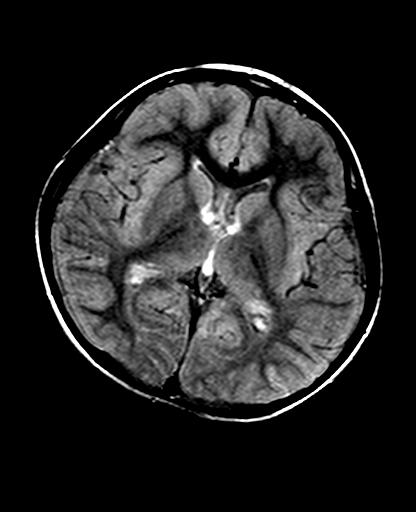

标题: PED2848:脑内病变2

头痛10天、间断呕吐2天。f 6岁

入科化验血清铜及铜兰蛋白均减低,脑脊液正常,血清神经原烯醇化酶明显增高。wbc:5.94x109/l、

临床表现及实验室检查符合肝豆状核变性

符合肝豆状核变性。

mri未见明显异常。但临床支持考虑肝豆状核变性。

肝豆状核变性可能性大。